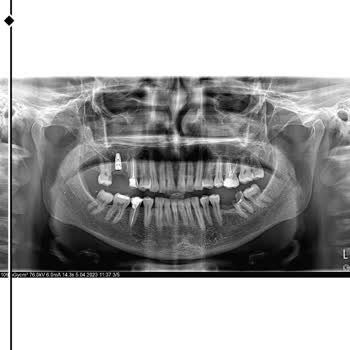

25 Şubat 2026 tarihinde 8 yaşındaki çocuğumu diş tedavisi için Esenler Medipol Hastanesi Çocuk Diş Hekimliği Bölümü’ne götürdüm. Uzman doktorların gözetiminde stajyerlerin işlem yaptığını, röntgende görünmeyen bir kanal tedavisinin burada tespit edildiğini söyleyerek bizi bu işleme yönlendirdiler. H...